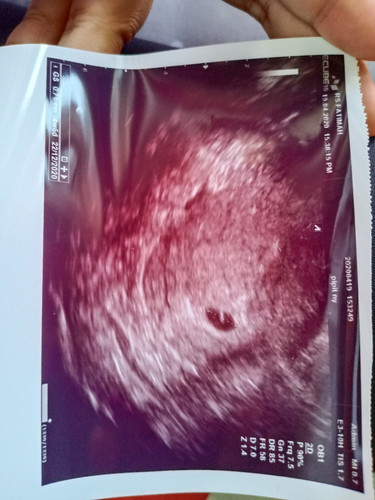

Moms, saya sedang hamil 29w3d. Kemarin kontrol rutin dan kata dokternya ari ari si baby masih dibawah & nutupin jalan lahir. Dokter si bilang masih bisa geser ari arinya. Tp kalo evaluasi bulan depan gak geser juga, gk boleh maksain lahiran normal. Sebenernya mau normal atau SC sama aja perjuangannya. Moms ada juga gak yang punya pengalaman ari ari dibawah/plasenta previa diusia TM3. Sharing dong moms #bantusharing